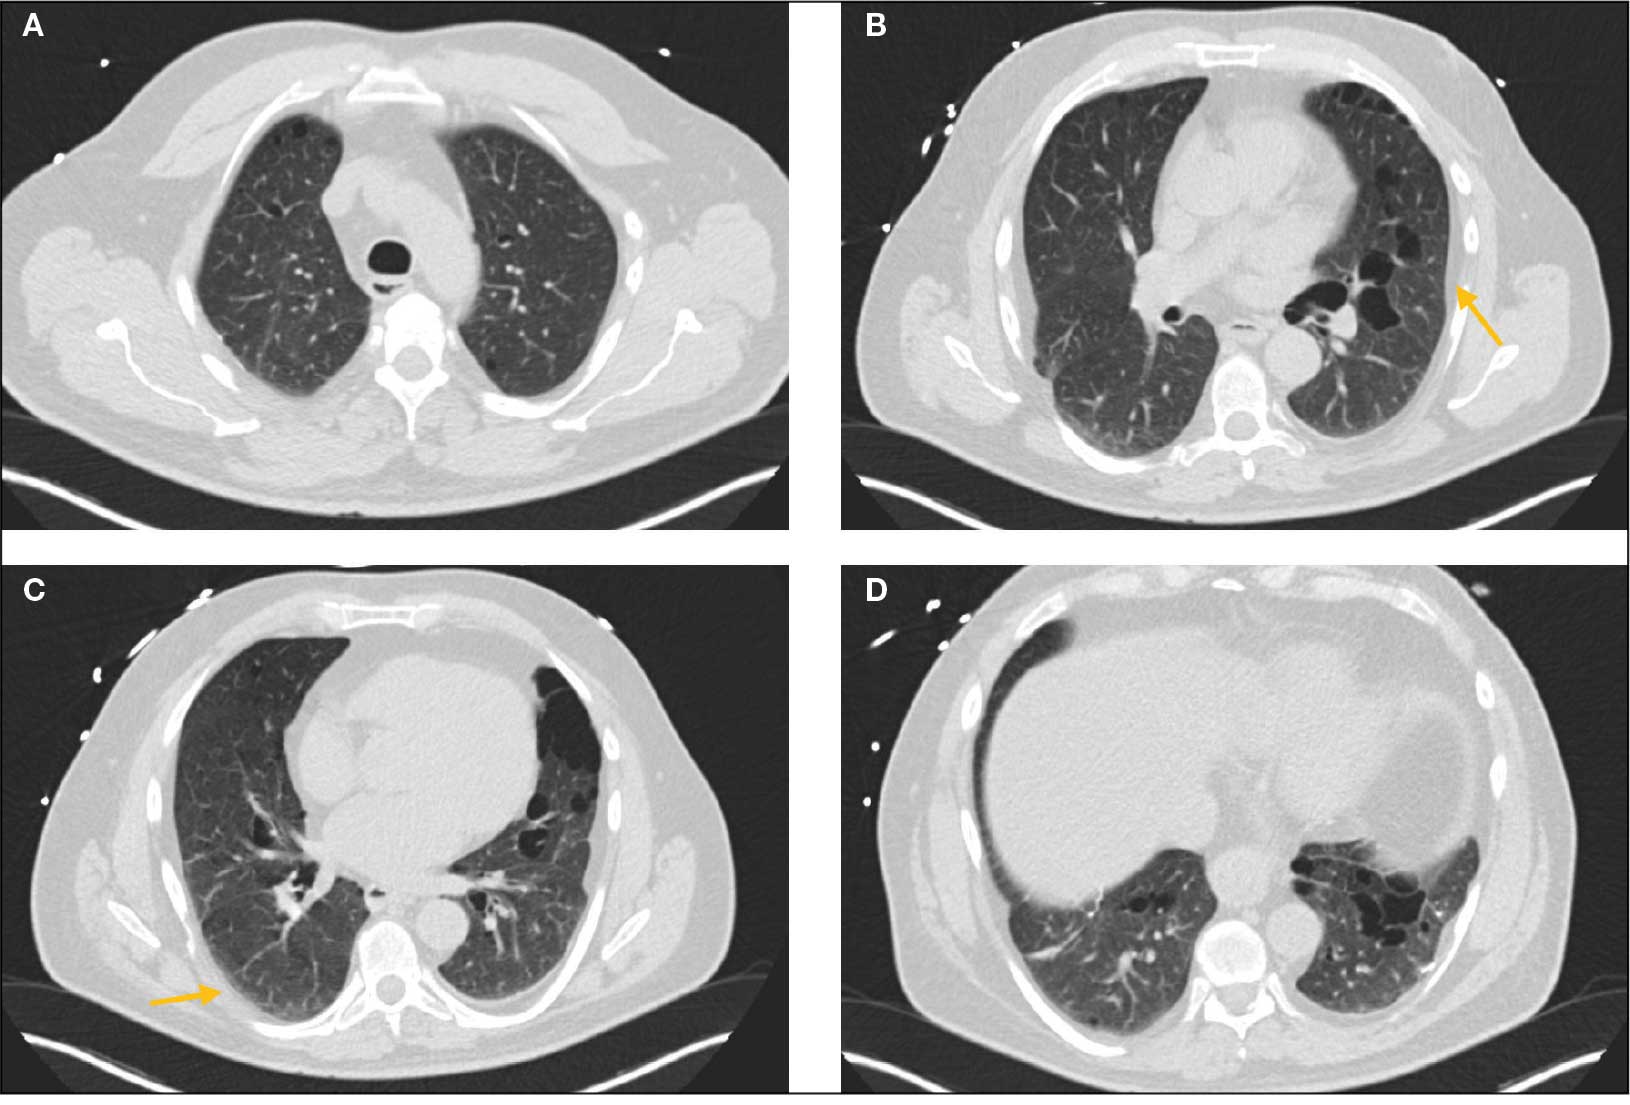

Laboratory results revealed a normal α-1 antitrypsin level: 133 mg/dL (reference, 83-199 mg/dL), with a Pi*MS phenotype and undetectable antinuclear antibodies. The most recent chest computed tomography (CT) in 2019, displayed paraseptal and centrilobular emphysema, scattered blebs, and scarring consistent with prior pleurodesis procedures (Figure 2).